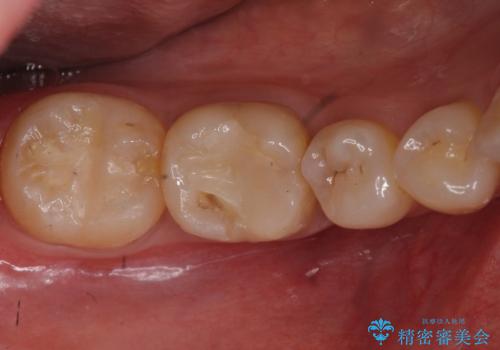

銀歯を白くしたい セラミッククラウンでのやり替え